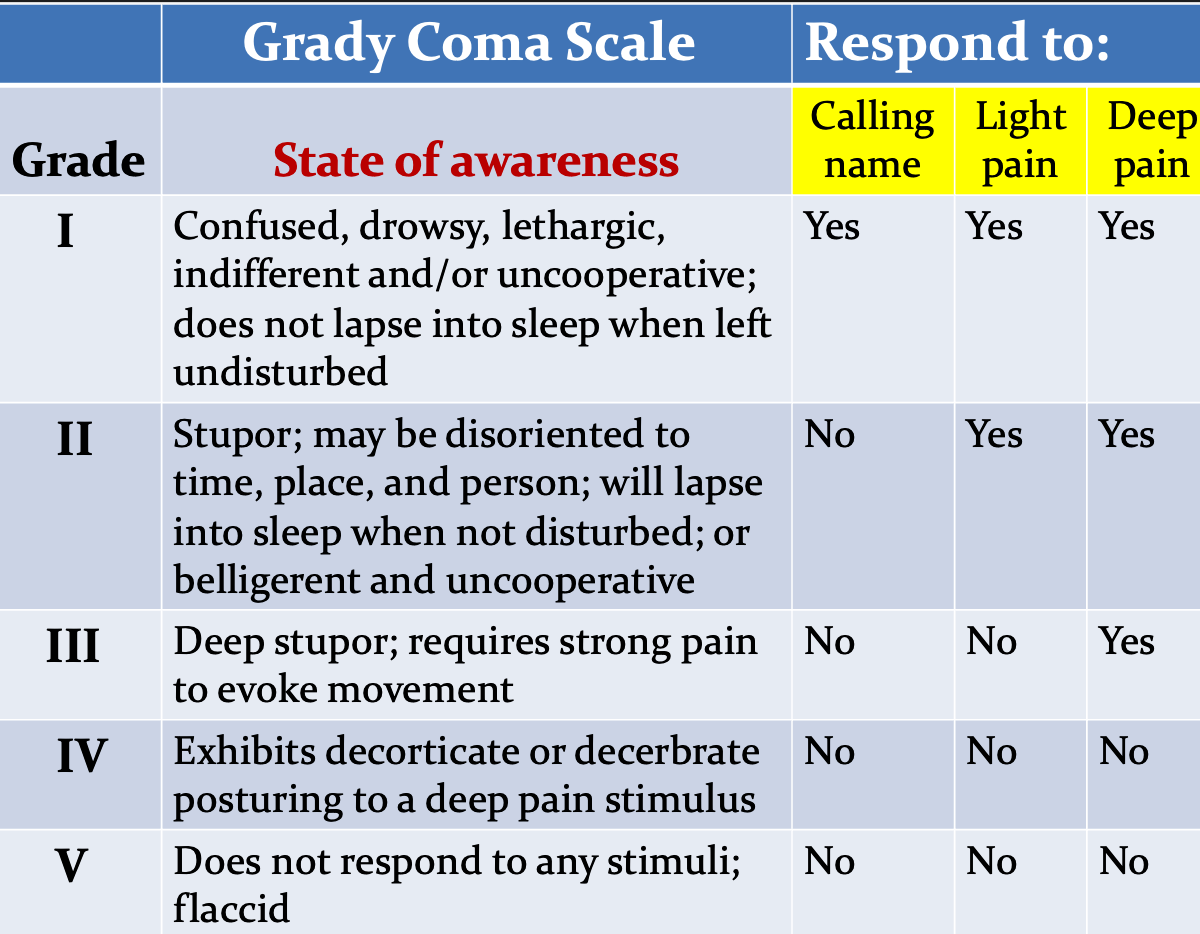

Scores

B) Grady Coma Scale